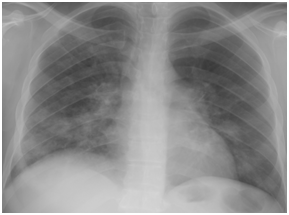

Figure 4A Chest X-ray film on day two from suffering attack of low grade fever.

Figure 4B Follow up Chest X-ray at time of diagnosing H1N1 pneumonia 6 days later.

Figure 4 H1N1 radiological pictures in a diabetic 28-year-old transplant recipient.